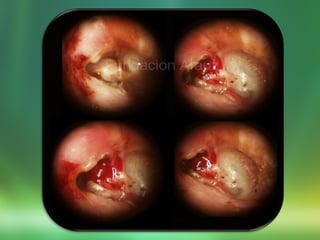

DIAGNÓSTICO:

Otoscopía

Endoscopía transtimpánica:

Perforaciones o retracción en la parte fláccida de la

MT.

Valorar:

Estado de la mucosa del OM

Destrucción o erosión en la pared posterior

del CAE